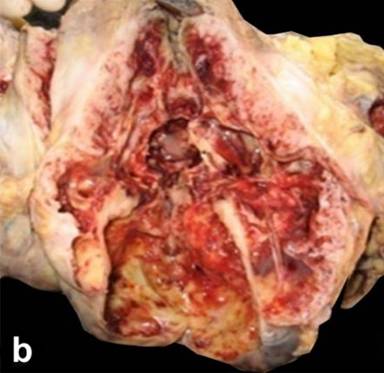

Gross and Microscopic Pathology (Table 3, Figure 2ab, Figure 3a-d)

On hematoxylin and eosin (H&E) stained tissue sections, the tumors showed variable cellularity comprising exclusively or predominantly of fusiform/spindled cells in short intersecting fascicles and focal storiform pattern (most common; 13/19, 68.4%) resembling a smooth muscle tumor, whereas six tumors (31.6%) demonstrated variable admixture of spindled and epithelioid stromal cells, simulating sarcomatoid carcinoma. In 7 (36.8%), the lesions were characterized by foci of perivascular hyalinization and/or nuclear pallisading reminiscent of a neural tumor. Areas of myxoid degeneration, cyst formation, and hemorrhage were observed in 5 cases (26.3%), coagulative necrosis in 4 (21.1%), whereas 3 tumors (15.8%) exhibited moderate to marked nuclear pleomorphism. Infiltration of tumor cells with mast cells (Giemsa stain) and inflammatory cells were noted in 5 (26.3%), thus simulating inflammatory pseudotumor (myofibroblastic tumor). In contrast to gastrointestinal counterparts, pure epithelioid morphology (so called leiomyoblastomas) and Skenoid fibers were not seen in any of the pEGIST. Using threshold values of 2 mitotic figures/50 high power field (HPF), 11/15 (73.3%) showed more than 2 mitotic figures/50 HPF, whereas 4/15 (26.7%) had 2/50 HPF or less, and in rest (4/19, 21.1%) the mitotic activity was not described.

Figure 3. Photomicrographs from the tumor in the pancreas showing pancreatic tissue at the periphery and the cellular lesion (40x) (a.). The tumor showed predominantly fusiform spindle shaped cells in intersecting fascicles resembling a smooth muscle tumor (b.), with foci of nuclear pallisading reminiscent of a neural tumor (c.), and myxoid areas (d.) (H&E, 100x). |